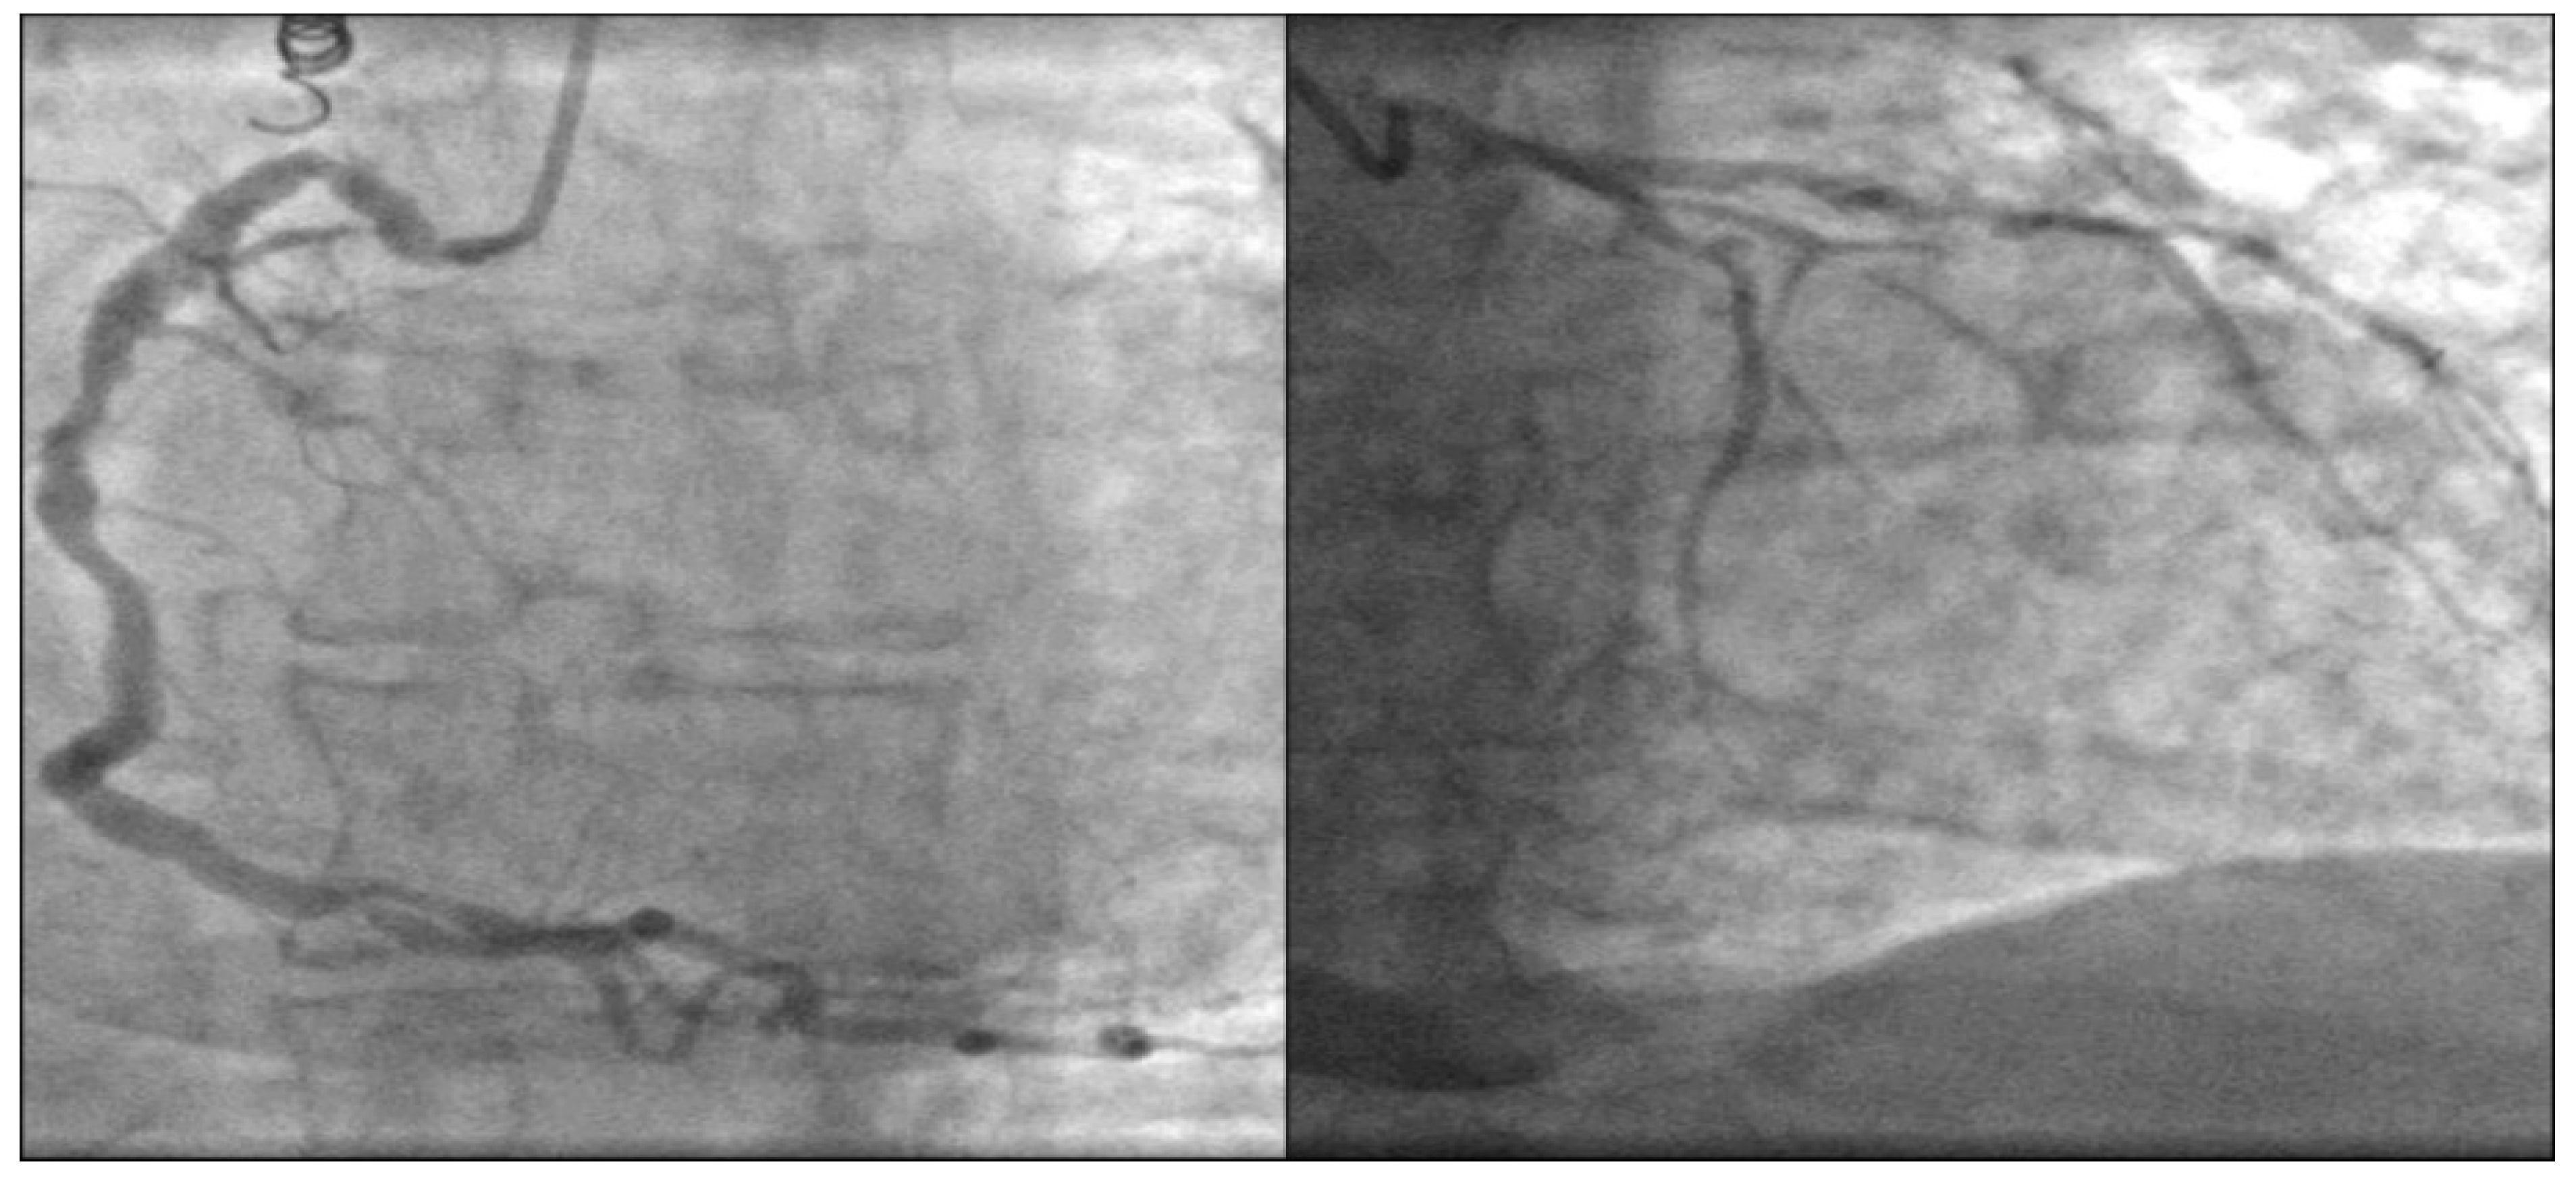

These findings were confirmed by transesophageal echocardiography (TOE), aortic valve is tricuspid with severe calcinosis, aortic valve area (AVA) was 1.1 cm2 (Figure 3).

Coronary angiography showed extremely diffused three-vessel coronary artery calcification (Figure 4).

Figure 3. TOE: aortic valve is tricuspid with severe calcinosis. AVA was 1.1 cm2.

Figure 4. Coronary angiography. Diffused coronary artery calcification.